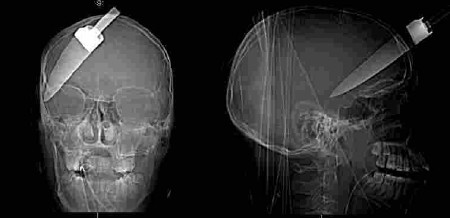

Victim 1 sustained a head injury and was taken to hospital where he was detained. The knife was still embedded in his head; Victim 2 received a chest injury but was later discharged from hospital; Victim 3 suffered minor injuries to the shoulder and was discharged the following day.

"Because he was carrying a knife he used it and in his frenzy he stabbed one boy so hard that it was embedded in his skull and the handle came away as he tried to withdraw the knife.

"Only the skill of a surgeon saved his life but he will need considerable support for the rest of his life. No one hearing these facts will be surprised at how seriously the court has taken this case in sentencing this seventeen year old boy to a serious term of imprisonment.